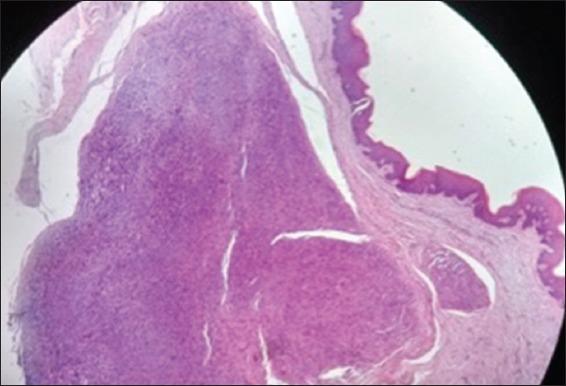

Neural tumors in the oral cavity occur both in the soft tissues and in the jaw bones. They occur as painless, smooth surface swelling in the soft tissues of the mouth, exhibiting a slow rate of growth and mild expansion of the cortical plates. Here, we report a rare case of a cellular variant of schwannoma in a young Indian female patient who presented with an asymptomatic nodule in the mid-palatine raphe region of the hard palate, mimicking a fibroma, thus creating a dilemma in the diagnosis.

口腔中的神经肿瘤可发生于软组织和颌骨。它们表现为口腔软组织中无痛、表面光滑的肿胀,生长速度缓慢,皮质板轻度扩张。在此,我们报告一例罕见病例,一名年轻的印度女性患者患有细胞型施万细胞瘤,该患者硬腭中缝区域出现无症状结节,类似纤维瘤,从而在诊断上造成了两难局面。